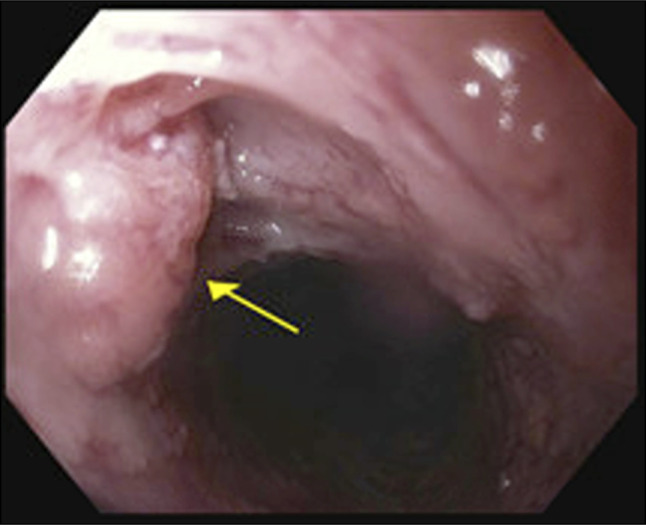

摘要食管壁内假性憩室病(EIPD)是一种罕见的疾病,在内镜下表现为食管壁内有许多小的流出物。虽然通常与吞咽困难等良性症状相关,但EIPD与食管恶性肿瘤有关,既是一种易感疾病,也是相关的共存诊断。然而,两者之间的联系尚不清楚。本病例报告详细介绍了一名有EIPD病史的患者,在整个食管高度发育不良的情况下发展为多灶性浅表鳞状细胞癌。

Esophageal intramural pseudodiverticulosis (EIPD) is a rare disease characterized endoscopically by numerous small outpouchings within the esophageal wall. While typically associated with benign symptoms such as dysphagia, EIPD has been linked to esophageal malignancy, both as a predisposing condition and associated coexisting diagnosis. However, the association is not clear. This case report details a patient with a history of EIPD who developed multifocal superficial squamous cell carcinoma in the context of high-grade dysplasia throughout the esophagus.